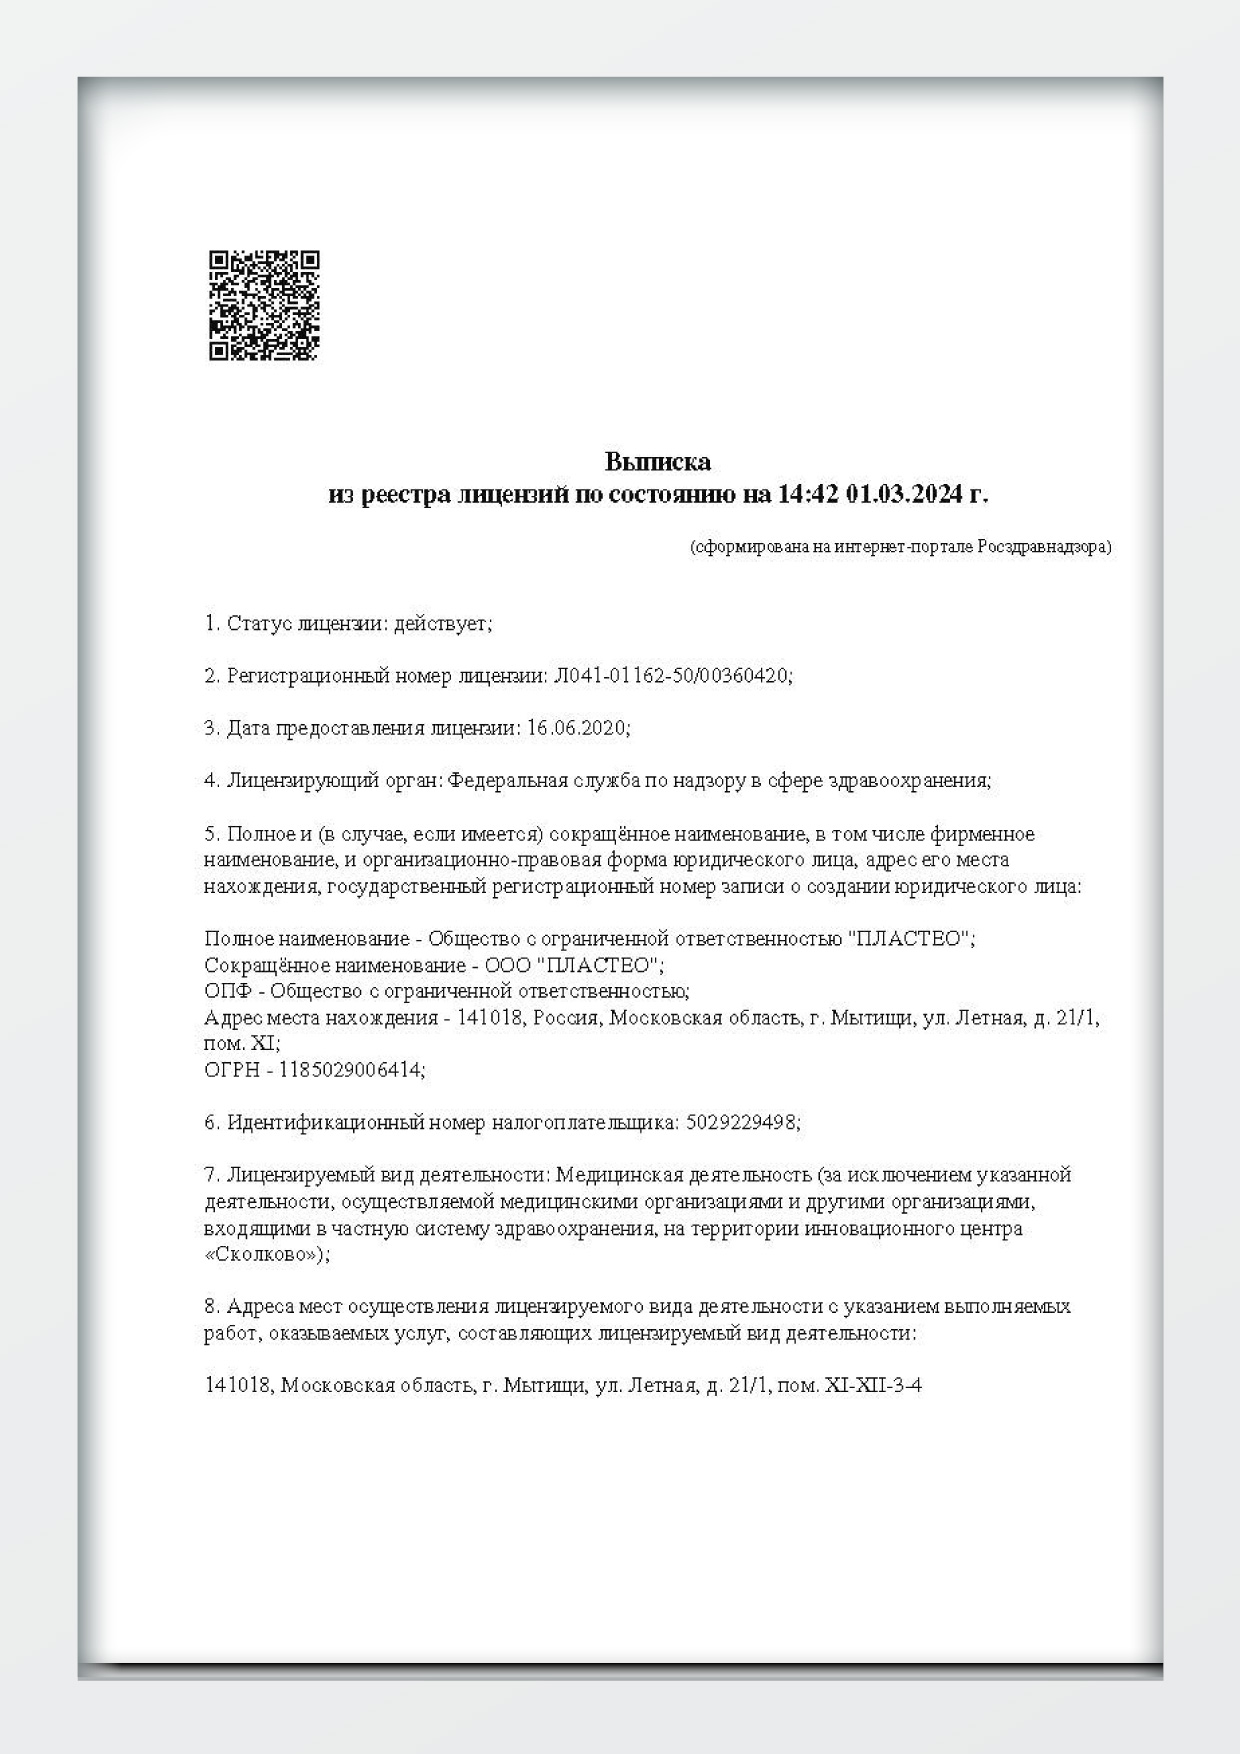

Наши лицензии